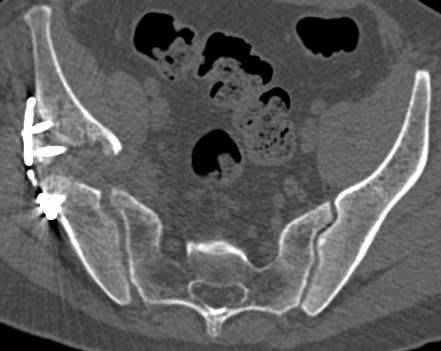

Интересно было бы посмотреть рентгенограммы до операции. У меня впечатление, что я не все вижу, что тут есть... Уважаемые Господа "тазисты" и "тазологи", к какому типу переломов вертлужной впадины по Летурнелю вы бы отнесли это случай?

Из переломов проходящих через крыло и/или заднюю стенку ни простой перелом "передней колонны" (явно имеется пером задней стенки, и не видно перелома седалищной или лонной), ни простой "поперечный", ни ассоциированный "Т-образный" (т.к есть перелом крыла и не видно перелома седалишной), ни ассоциированный "задняя колонна+задняя стенка", на ассоциированный "поперечный+задняя стенка", ни ассоциированный "передняя колонна+задняя гемисфера" (не видно перелома седалищной), ни ассоциированный "обе колонны" (не видно перелома лонной седалищной) не подходят под эту классификацию....

к таковым себя не причисляю, но...обычное дело для нашей страны - выкладывать 3D и не показывать стандартные проекции Judet. Дигност представляет те ракурсы, которые по-его мнению наиболее информативны, более того комп сам достраивает какие-то мелкие повреждения по 3D по своему усмотрению. По данной реконструкции можно предполагать высокий двухколонный перелом с оскольчатыми передней и задней колоннами, оскольчатую высокую переднюю колонну с задним полупоперечником или одно из перечисленных с вовлечение КПС. У меня впечатление за второй вариант, но нужно обследовать нормально - проекции, сканы.

высылаю дополнительно сканы.

итак, второй вариант: высокий двухколонный с вовлечением КПС... Ни одно из основных повреждений не репонировано, кроме задней стенки. Скорее всего попытка реконструкции вертлуги сейчас будет очень травматичной и не очень эфективной, т.е. вероятный риск более значим, чем ожидаемая польза... Лучше подождать, и потом сразу эндопротез